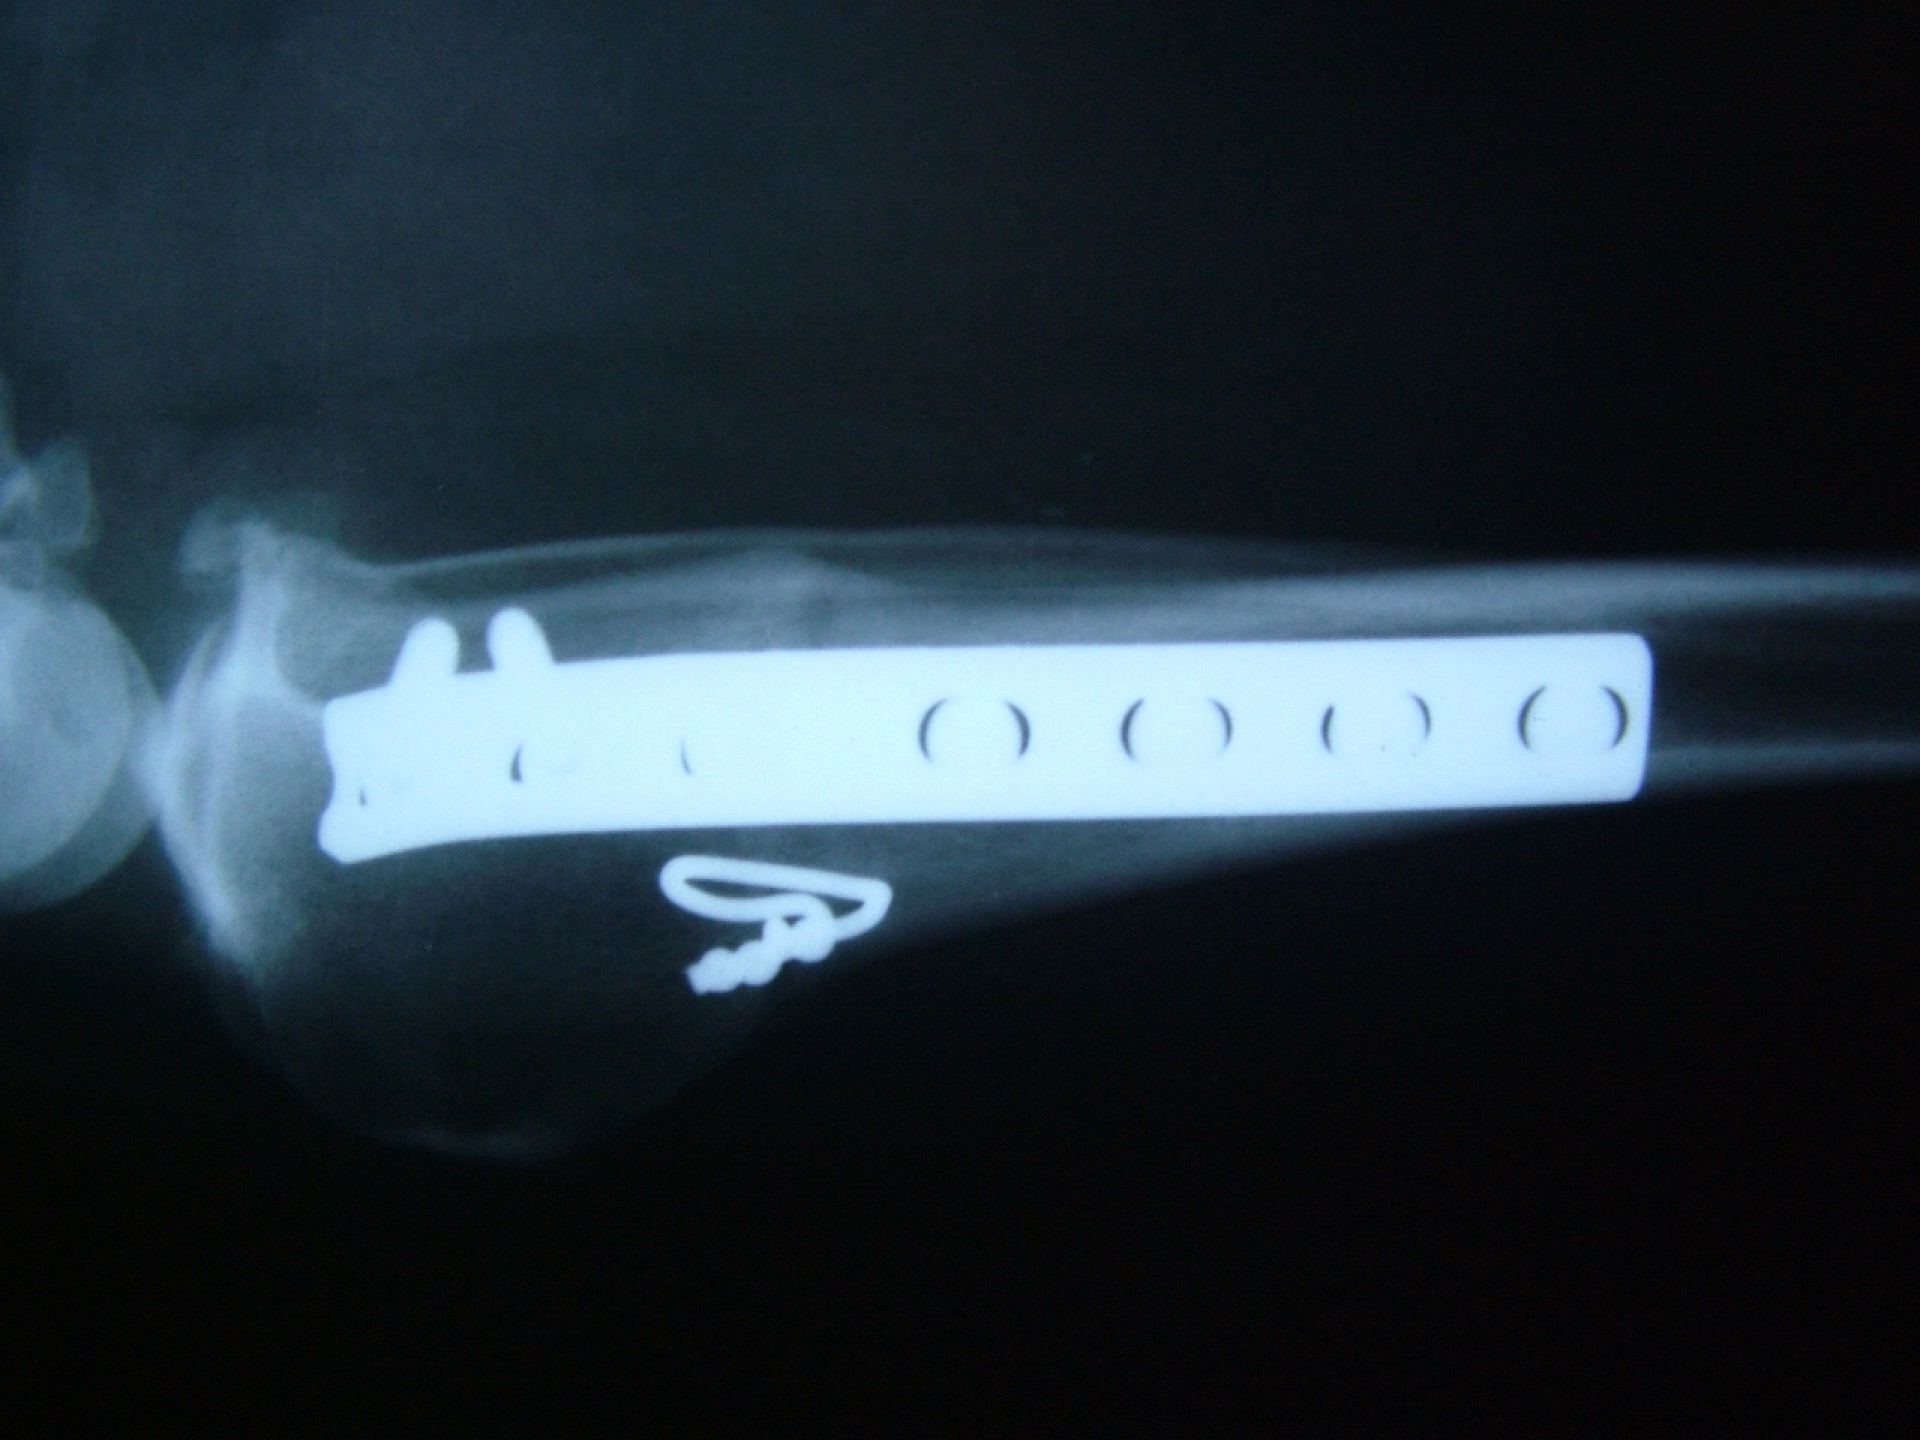

Az utóbbi 25 év egyik legnagyobb előrelépését jelentette a kereszteződőszalag szakadás műtéti megoldásában az amerikai származású Barclay Slocum által kifejlesztett műtéttechnika, mely alapja a szakadásra hajlamosító tényezők és a szalagra ható fizikai erők vizsgálata. Barclay Slocum olyan műtéti technikát dolgozott ki, mellyel a térdízületet az elülső kereszteződőszalagra ható erőkhöz igazítja. Vizsgálatai alapján a sípcsont ízületi felszínének meredeksége (tibia plató szög, tibial plateau angle, TPA) és az elülső kersztezőszalag szakadása között egyértelmű összefüggés mutatható ki. A műtét alapja, hogy a sípcsont ízületi felszínét a sípcsontból kivágott ék, majd azt követő lemezes osteosynthesis segítségével a sípcsont hossztengelyére megközelítőleg merőlegesre állítja be, csökkentve ezáltal a szalagra ható erőket (cranial wedge tibial osteotomy, CWTO).Ezt a technikát továbbfejlesztette: a sípcsonti ízületi felszín szögellésének korrekcióját egy speciális félkör alakú fűrész segítségével, az ízületi felszínt is magába foglaló sípcsonti részlet kivágásával, elforgatásával és rögzítésével oldatta meg (tibial plateau leveling osteotomy, TPLO).